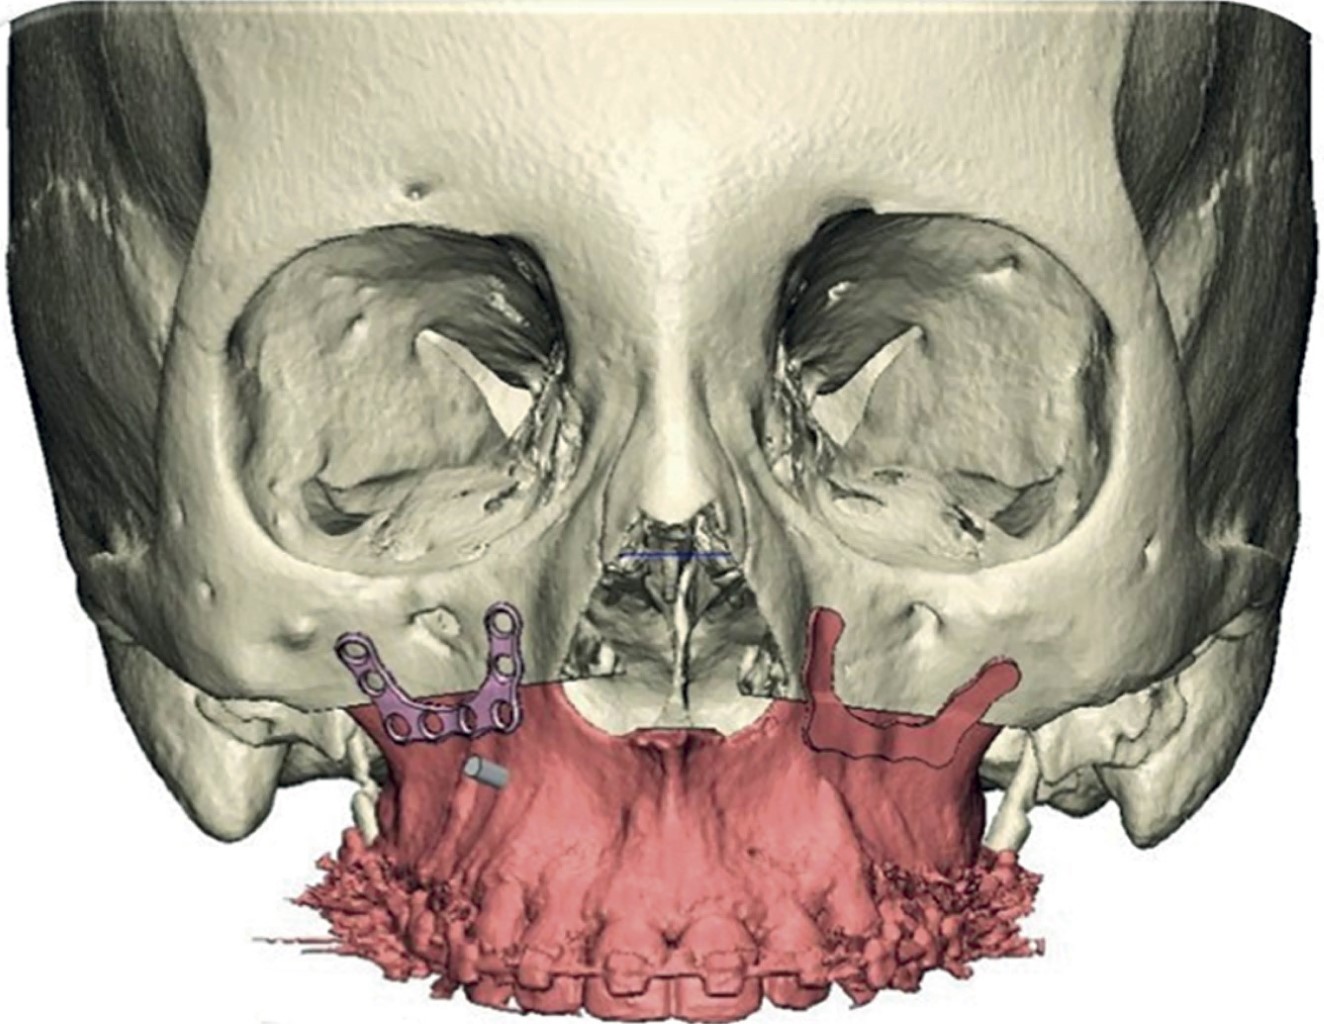

Introduction: currently, computer-aided planning of orthognathic surgery helps us obtain better results, avoiding errors that could occur with conventional orthognathic surgery planning. With virtual planning of orthognathic surgery, we obtain surgical guides that help us stabilize the maxillary segments during surgery to avoid recurrences. Currently, the use of cutting guides and customized plates in Le Fort I osteotomy eliminates the need for occlusal surgical guides, minimizing surgical time, making the surgery more agile, and improving results. Clinical case: a 20-year-old female patient was diagnosed with maxillary vertical excess and anterior open bite. Surgery was performed using virtual surgery to plan a 4 mm Le Fort I impaction osteotomy, using custom-made titanium plates and cutting guides during the procedure. Results: the advantages of using this management protocol in orthognathic surgery are: reducing pre- and intraoperative work time, minimizing errors in surgical movements, developing simpler and more precise surgical procedures, avoiding injuries to the anatomical structures involved, transferring the results of the virtual simulation in the manufacture of cutting templates to the operating room, obtaining highly satisfactory results, carrying out and establishing an optimization protocol and finally obtaining a database of surgical patients. Conclusions: it is a versatile technique, with a minimum degree of difficulty and easy to perform.

Figure 4